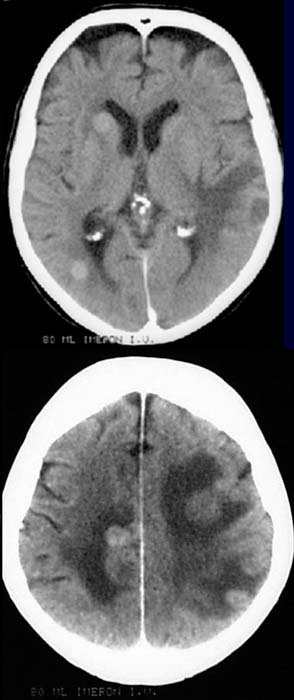

54 jähriger Patient mit bekanntem Bronchialkarzinom. Starke Kopfschmerzen.

CCT mit Kontrastmittel.

Multiple

hyperdense Kontrastmittel-aufnehmende Raumforderungen temporal

links, frontal rechts, Stammganglien rechts, occipital rechts und hochparietal

beidseits. Hypodense

Areale um die Raumforderungen.

Hirnmetastasen bei bekanntem Bronchialkarzinom mit perifokalen Ödemen.